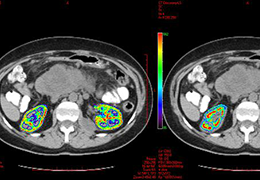

View X-Ray CT & MRI Scans Fast and Easily

Designed for surgeons, Pro Surgical 3D makes it easy to view patient scans quickly. Pro Surgical 3D facilitates the optimal 3D treatment and assessment workflows based on X-ray CT and MRI scans – and best of all, it’s FREE!

Designed mainly for CT and MR DICOM modalities.

Side-by-side comparative assessment for pre- and post-operative scans.